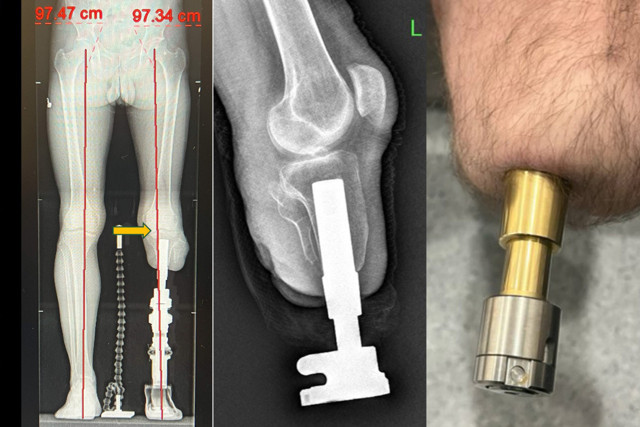

Abone olKlasik soket protezlerin yol açtığı ağrı, yara ve yürüme zorluklarına bir alternatif sunan osseointegrasyon yöntemi, amputasyon hastalarına umut veriyor. Medipol Mega Üniversite Hastanesi Ortopedi ve Travmatoloji Uzmanı Prof. Dr. Adnan Kara, Türkiye’de yeni nesil osseointegrasyon protezini ekipleriyle uygulayan ilk merkez olduklarını belirterek, “Bu yöntemle hastalar adeta kendi bacaklarıyla yürüme hissine kavuşuyor” dedi. Bu yöntemde, kemiğe yerleştirilen implant sayesinde yük doğrudan kemiğe aktarıldığından, çok daha doğal ve konforlu bir yürüyüş mümkün oluyor.

Osseointegrasyon yönteminin dünyada sayılı merkezlerde uygulandığını vurgulayan Prof. Dr. Kara, “Bu işlem sadece ortopedik cerrah ile değil, fizik tedavi uzmanı, anestezi hekimi ve deneyimli fizyoterapistlerden oluşan bir ekip ile mümkün. Multidisipliner bir yaklaşımla başarılı sonuçlar alıyoruz” diye konuştu. Osseointegrasyon protezinden kimlerinfaydalanabileceğine de değinen Prof. Dr. Kara, yöntemin en çok daha önce soket protez kullanmış ancak çeşitli sorunlar yaşamış genç ve aktif hastalara önerildiğini söyledi. “Ciltte yara oluşumu, yürüyüş sırasında ağrı, uyumsuzluk nedeniyle erken yorulma gibi sorunlarla bize gelen hastalarda bu yöntem oldukça etkili. Klasik protezlerle sadece birkaç dakika yürüyebilen hastalar, bu yeni sistemle hayatlarına tekrar karışabiliyor” dedi.

Osseointegrasyon protezlerinin getirdiği his avantajına da değinen Prof. Dr. Kara, “Bu yöntemle hastalar bir yıl içerisinde bastıkları zeminin kum, çakıl ya da düz olup olmadığını ayırt edebiliyor. Hislerin kemiğe iletildiği veriler sayesinde vücut o bacağı kendi uzvu gibi hissediyor. Bu da hastanın yürüyüşünü ve psikolojisini büyük ölçüde olumlu etkiliyor” dedi. Osseointegrasyon protezlerinin yapıldığı uzuvlar hakkında da bilgi veren Prof. Dr. Kara,yöntemin uyluk, kaval kemiği, dizüstü ve dizaltı gibi bölgelerin yanı sıra üst kol amputasyonlarında da başarıyla uygulandığını aktardı.